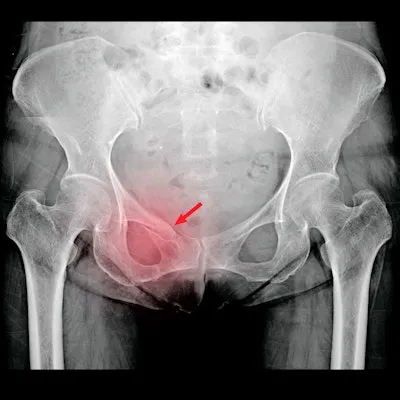

AI in Fracture Care - Bone Break Busters

AI revolutionizes fracture management by enhancing detection, classification, and assessment.

- Identifies occult & stress fractures (e.g., scaphoid, hip, rib) on X-ray & CT.

⭐ AI algorithms demonstrate high sensitivity in detecting occult hip fractures on plain radiographs, potentially reducing delays in diagnosis and treatment.

- AI significantly improves fracture detection, especially occult fractures, on radiographs and CT.